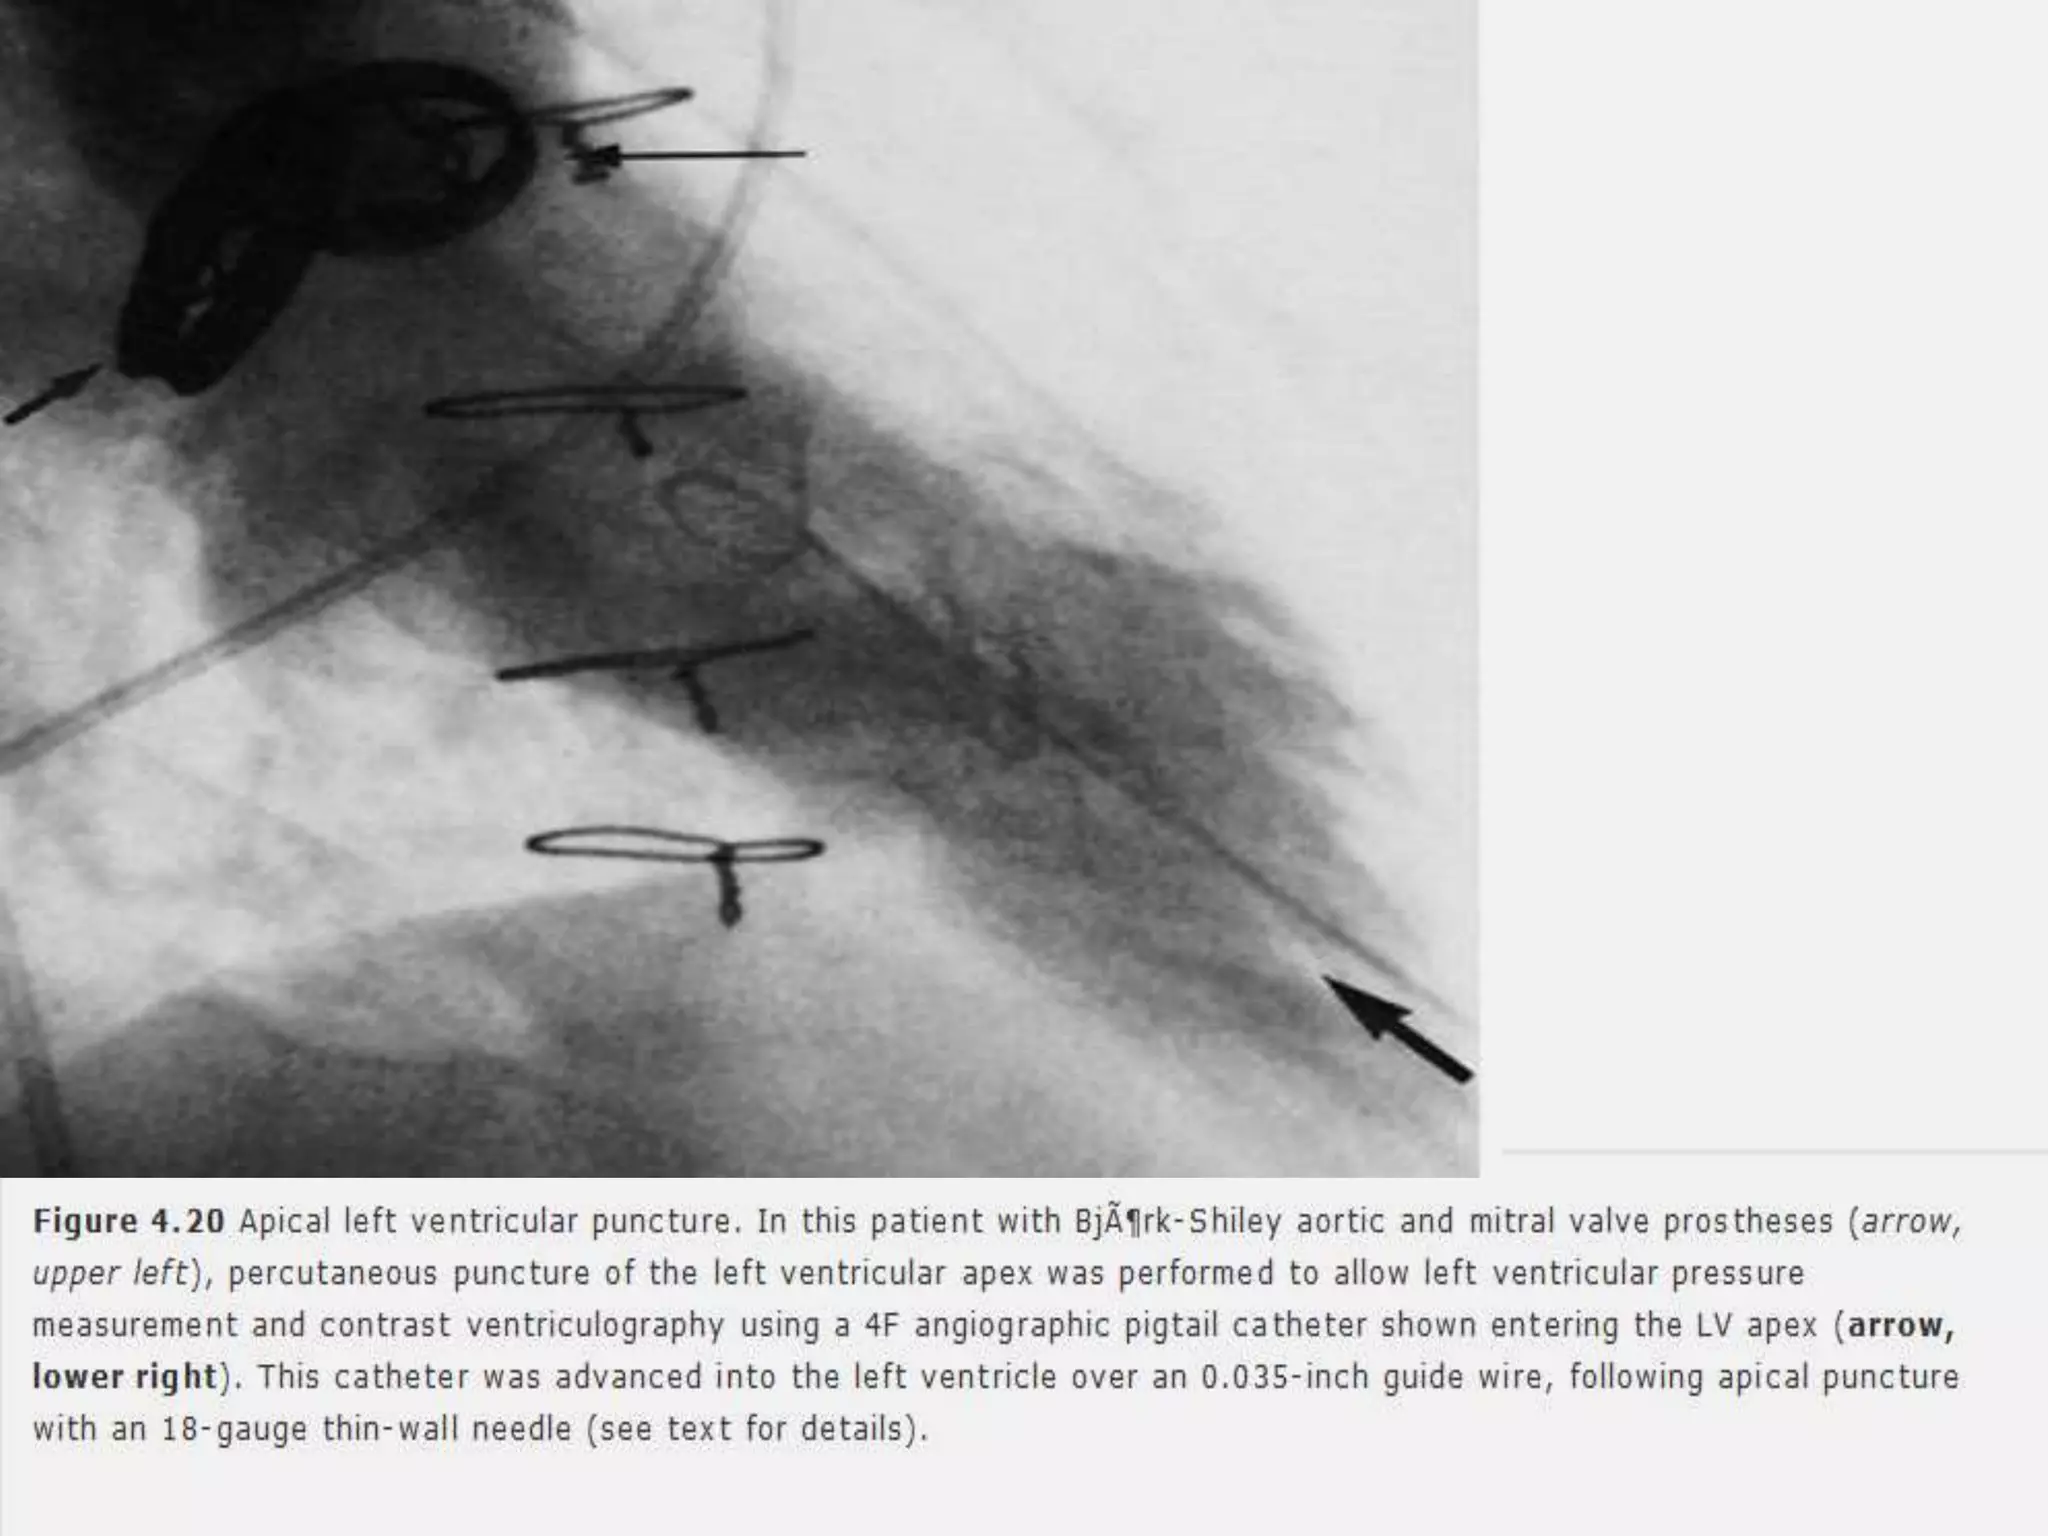

 Measure LV pressure and perform ventriculography in patients with

mechanical prosthetic valves in both the mitral and aortic positions that

prevent both retrograde and transseptal catheterization.

 Crossing of tilting disks to be avoided – catheter entrapment, occlusion of the

valve,possible dislodgement and embolization of the disc.

 Localization of LV apex by palpation or by echocardiography.

 18 G 6” inch Teflon catheter system is inserted at upper rib margin, directed

slightly posteriorly and toward the right second intercostal space.

 Needle and sheath are advanced into the LV.

 Stylet and the needle removed.

 Sheath connected for pressure measurement.

 Measure LVpressure and perform ventriculography in patients with mechanical prosthetic valves in both the mitral and aortic positions that prevent both retrograde and transseptal catheterization.  Crossing of tilting disks to be avoided – catheter entrapment, occlusion of the valve,possible dislodgement and embolization of the disc.  Localization of LV apex by palpation or by echocardiography.  18 G 6” inch Teflon catheter system is inserted at upper rib margin, directed slightly posteriorly and toward the right second intercostal space.  Needle and sheath are advanced into the LV.  Stylet and the needle removed.  Sheath connected for pressure measurement.